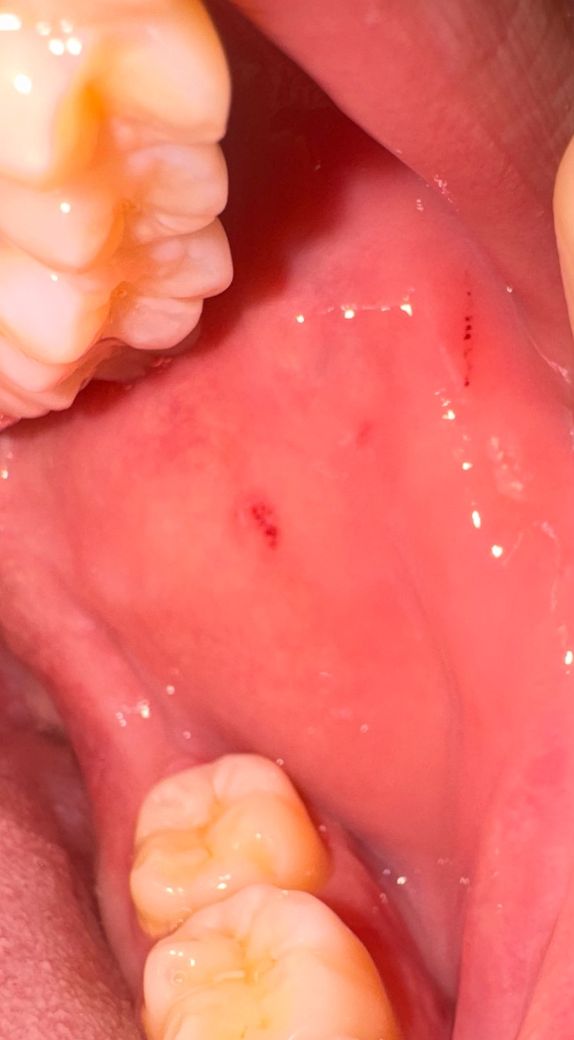

양치하다가 피가 나오길래 입 안을 봤더니 상처가

최근에 양치하다가 피가 나오길래 입 안을 봤더니 다른 날에는 보이지않던

상처가 있네요 통증이 있거나 하진 않은데 상처가 아니라 구내염일까요 무엇일까요??

사진만 보았을 때에는 협부 점막을 저작하여 발생한 상처로 생각이됩니다. 구내염이나 다른 질환보다는 외상성 상처로 사료되며 경과관찰 하시다가 크기 변화 또는 성상의 변화가 있을 시에는 가까운 치과 또는 구강악안면외과 등 내원하셔서 검사 받아보시도록 하시는 것을 권장드립니다.

위치상으론 볼을 씹어서 생긴 상처같습니다 반복적으로 씹을 경우 궤양이 생기거나 압흔이 생기기도 합니다

지금으로선 해당 부위 나을때까지 다시 또 볼을 씹지 않도록 주의해야 합니다